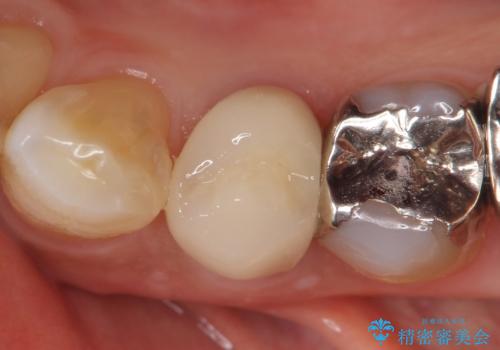

左下4の再根管治療を行い症状が治まったのち、オールセラミッククラウンによる補綴を行いました。

今回用いたオールセラミッククラウンはジルコニアフレームという白い素材の上にセラミックを盛っているため、審美性が非常に高いのが特徴です。

また、ジルコニアは人工ダイヤモンドの材料にも使われているほど高い強度を持っており、そのためオールセラミッククラウンは審美性だけでなく、奥歯やブリッジの補綴も可能とするクラウンです。